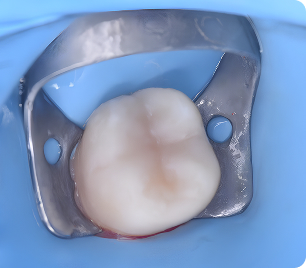

Кейін

Кейін